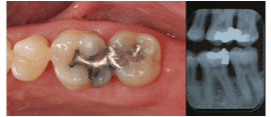

| Mandibular Right Second

Molar |

11 |

43.8% |

|